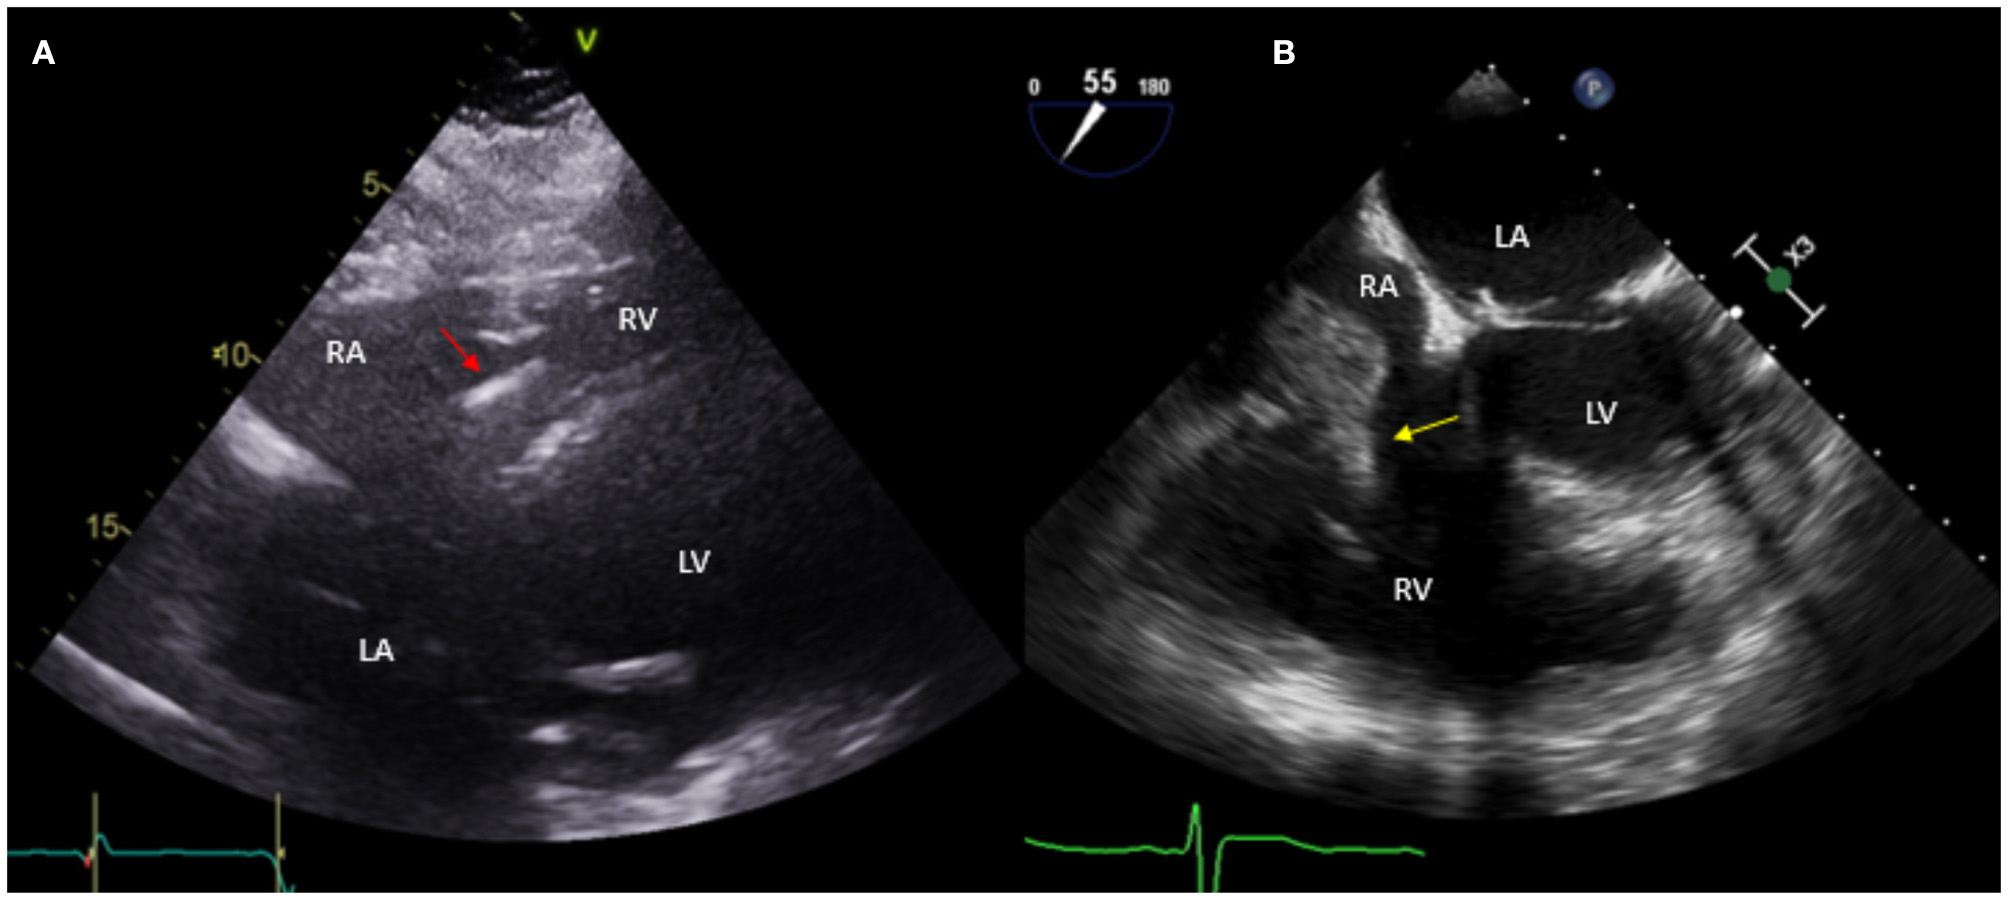

Figure 2

Fifty nine year-old male with a historyof ischemic cardiomyopathy (EF 35%) s/p ICD for primary prevention of sudden cardiac death who presented with fever and MSSE bacteremia. Initial TTE done (A) shows subcostal view with ICD lead in place (red arrow), without evident vegetations. Based on high clinical suspicion for CIED infection, a TEE was obtained (B) which showed a large vegetation attached to the ICD lead prolapsing into the right ventricle (yellow arrow). The patient was treated with IV antibiotics but given persistent bacteremia and large vegetation he underwent sternotomy with ICD system extraction and epicardial defibrillator placement.